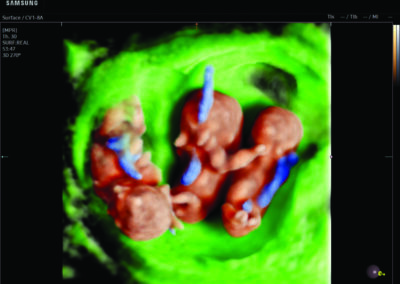

- Multiple births